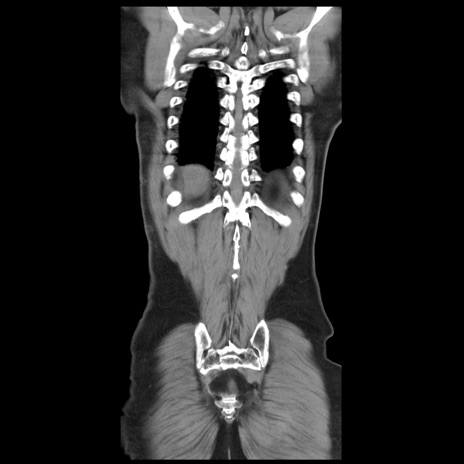

症例20(冠状断像)

【症例】 60歳代男性

【主訴】 腹部膨満、嘔吐

【現病歴】5日前頃より倦怠感を認め食事量減少し4日前の朝嘔吐、食事摂取困難となった。 3日前近医受診し点滴施行され整腸剤などを処方された。 当日他院を受診し、腹部膨満著明、炎症反応の上昇(CRP10.8、WBC11200)あり、紹介受診となる。

【身体所見】 意識JCS1 受け答えがはっきりしないBP 111/57mHg、 P 67bpm、、BT35.2°C、SpO2 97%(RA)、 腹部:膨隆、打診で鼓音あり、全体的に圧痛有り、腸蠕動音(-)、反跳痛ははっきりせず。

【データ】WBC 11400、CRP 14.20